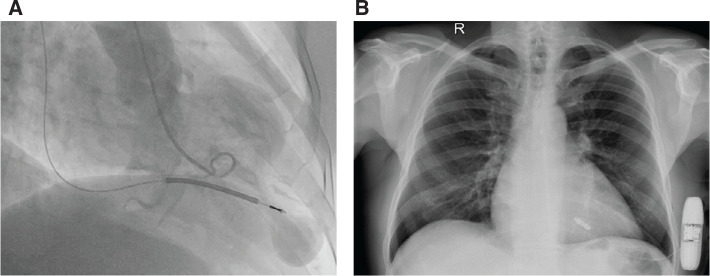

Cardiac implantable electronic devices (CIEDs) are essential tools in cardiology for tackling rhythm disturbances and have come a long way over the last decades. Technology is shifting toward leadless devices that spare the complications and limitations of traditional intravascular CIEDs. Herein, we report the simultaneous implantation of a leadless pacemaker (LP) and a subcutaneous implantable cardioverter-defibrillator (S-ICD) in two patients with hypertrophic cardiomyopathy, as well as their 2-year follow-up results, while explaining the preventive measures taken to steer around unwanted device interaction. Implantation of an S-ICD with an LP is reserved for unique cases but is a feasible approach when there is a contraindication for intravascular CIED implantation. Furthermore, this technique may be used in younger patients with cardiomyopathies in whom multiple generator replacements are expected, along with their known adverse effects.